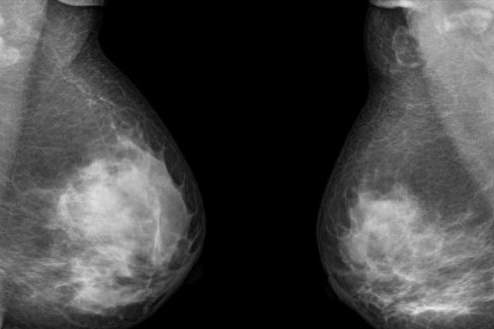

雙乳房切除術(shù)人數(shù)10年漲3倍 乳腺癌患者生存率幾無(wú)變化

美國(guó)過(guò)去10年來(lái)實(shí)施雙乳房切除術(shù)的女性人數(shù)增長(zhǎng)了3倍,但科學(xué)家們表示目前尚無(wú)法確定雙乳房切除術(shù)是否可以增加乳腺癌患者的生存幾率。

據(jù)合眾社報(bào)道,雖然許多女性乳腺癌患者選擇實(shí)施了雙乳切除術(shù)來(lái)降低乳腺癌的復(fù)發(fā)風(fēng)險(xiǎn),但目前的數(shù)據(jù)人無(wú)法確定該預(yù)防手術(shù)可以挽回乳腺癌患者的生命。